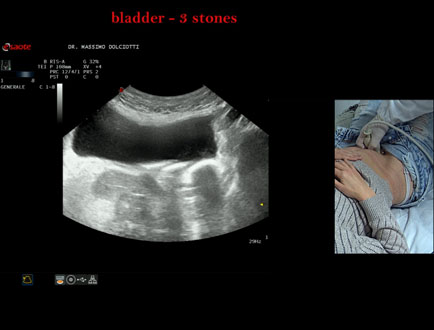

Data inserimento: 21/10/2025

Ecografia del: 15/10/2025

Strumento: Esaote MyLab Eight

Sonda: Convex Multifrequenza 1-8 MHz

Età Paziente: F 45 anni

Motivazione dell'esame: da alcuni mesi, disuria ed infezioni urinarie recidivanti.

Commento all'esame: le immagini ed il video documentano 3 immagini iperecogene, con cono d'ombra posteriore, da ricondurre a litiasi multipla della vescica.

Conclusioni: 3 calcoli della vescica (3 bladder stones).

Presentazione: Dr. Massimo Dolciotti - Ancona

Elaborazione digitale: Andrea Dini - Ancona